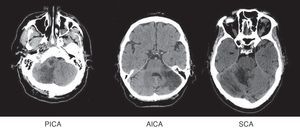

Patients were grouped by affected territory using Amarenco's Diagrams14: superior cerebellar artery (SCA), anterior inferior cerebellar artery (AICA), posterior inferior cerebellar artery (PICA), more than one affected territory (CA+) and simultaneous affectation of supratentorial territories (ST) (Fig. 1).

Affected vascular territories in order of prevalence were PICA (61, 49.2%), SCA (22, 17.7%), and AICA (13, 10.5%). Eleven patients were placed in the CA+ group (8.9%) and 17 (13.7%) experienced simultaneous affectation of supratentorial territories.